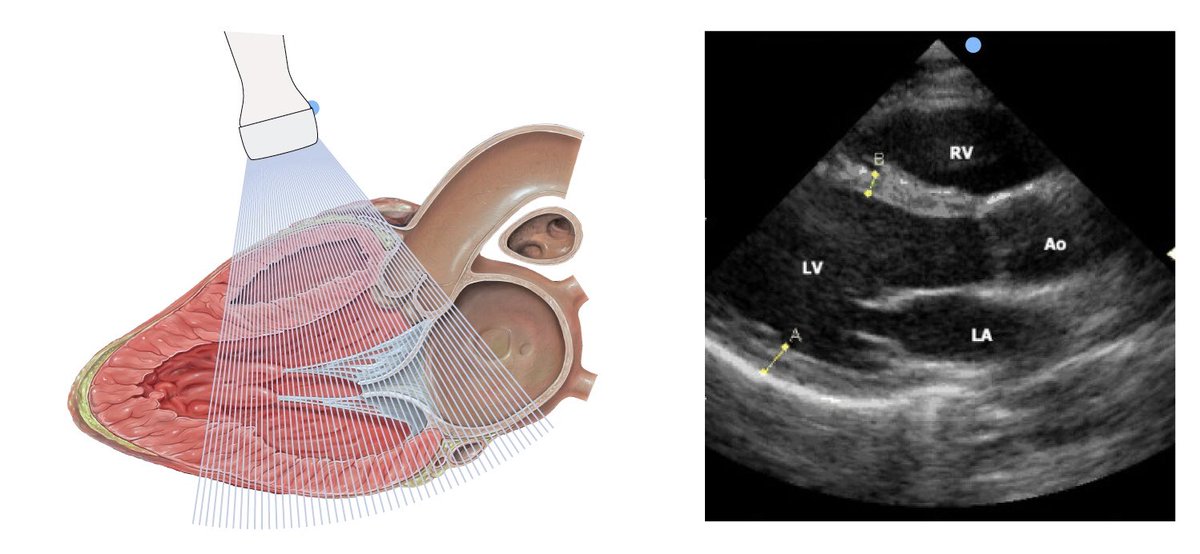

Echocardiography

يختصرونه إيكو Echo ، هذا الجهاز يستخدم الموجات فوق الصوتية ultrasounds UT عشان يعطينا صور متحركة للقلب وكمية ضخه للدم وسلامة الصمامات valves

الإيكو هو أسهل وأسرع وأكثر طريقة تستخدم لمعرفة الـ Ejection Fraction للقلب 😊